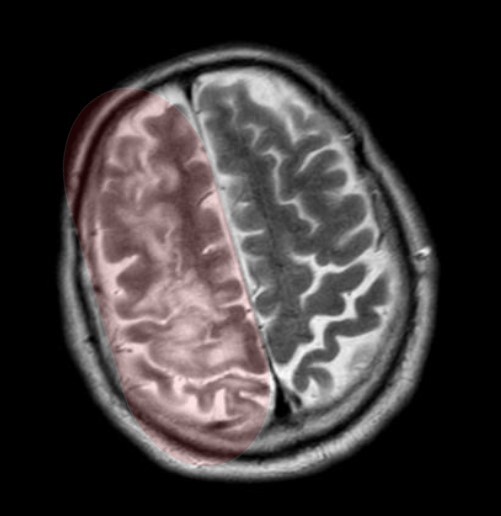

На 3й день после травмы из комы так и не вышла, посему сделали МРТ, на котором обнаружились участки повышенного сигнала на Т2-взвешенных изображениях на границе серого и белого вещества фронтально и темпорально справа, а также в область правого таламуса и в заднем отделе мозолистого тела т.н. сплениуме:

которые визуализировались и на FLAIR:

Очаги показывали также ограниченную диффузию на DWI-изображениях:

Ну и в довесок на SWI-изображениях (специальная импульсная последовательность, взвешенная по магнитной восприимчивости, усиливает сигнал от продуктов распада гемоглобина, что значительно повышает способность распознавать мельчайшие кровоизлияния в головном мозге) были выявлены очаги микрокровоизлияний в поражённых участках + в верхней ножке мозжечка и вдоль кортико-спинального тракта справа (чёрные пятна на изображениях):